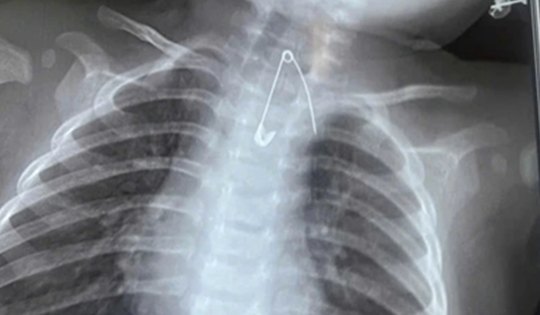

Bé trai 7 tuổi xẹp phổi trái, bác sĩ gắp ra thứ "đáng sợ" bên trong

16/02/2026 02:00

Bé trai 7 tuổi ở Nghệ An nhập viện trong tình trạng khó thở, tím tái. Bác sĩ ngay lập tức lấy thành công mảnh nhựa sắc nhọn, kịp thời ngăn suy hô hấp và biến chứng nặng.